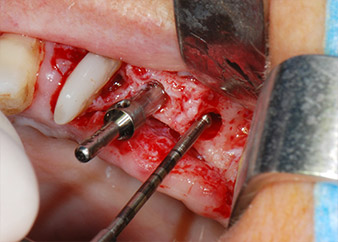

Имплантологичното ложе е подготвено в позиции 25 и 26 с ротиращи инструменти, използвайки обратен наконечник 20:1 с усъвършенстван и мощен имплантологичен мотор (Implantmed, W&H) (Фиг. 8).

Имплантите (Restore, Keystone Dental, диаметър 3,75 mm, дължина 8.0 mm) са поставени с имплантологичен мотор

(Фиг. 11 и 12).